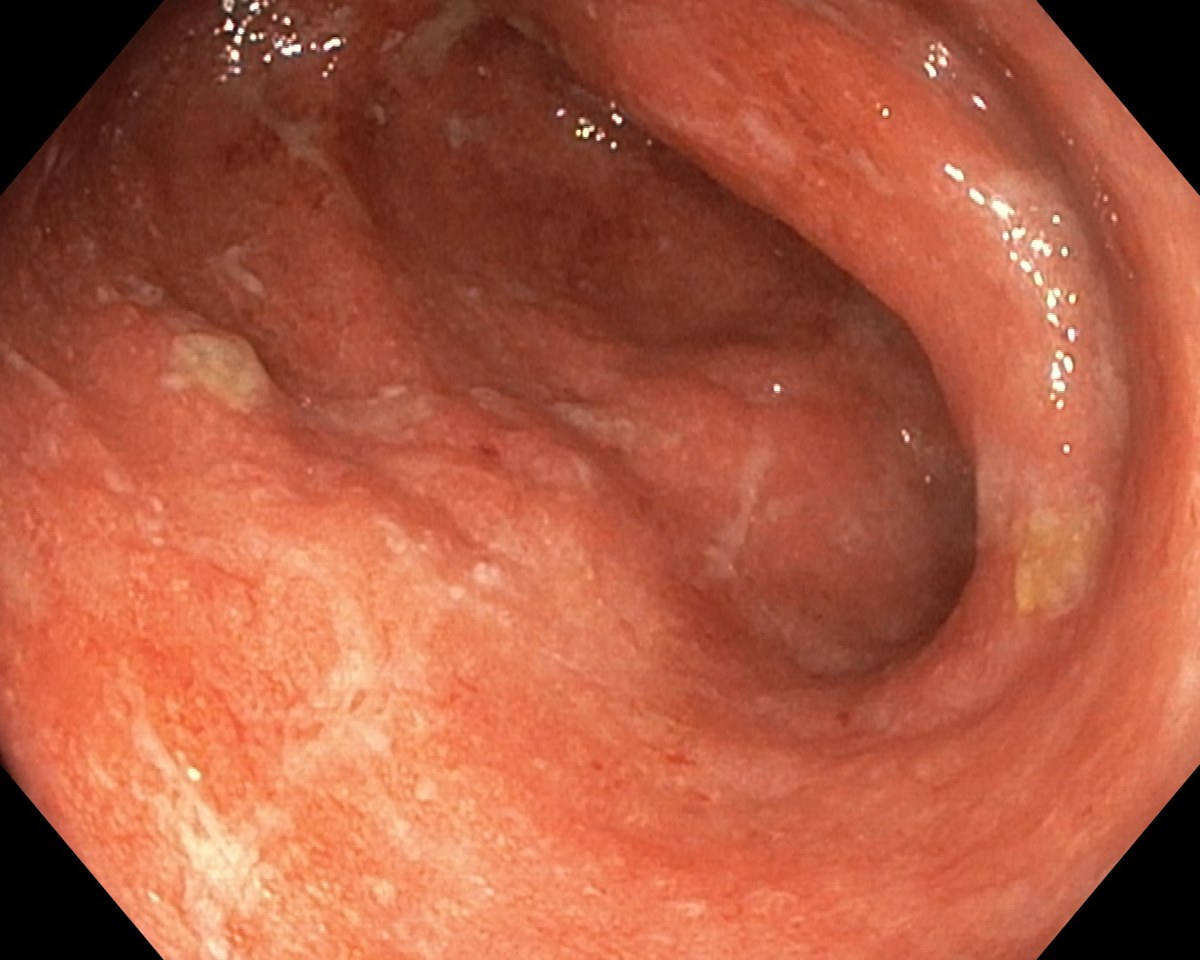

A Distal Ulcerative Colitis, Proctosigmoiditis Ulcerosa

A Distal Ulcerative Colitis.

A Distal Ulcerative Colitis